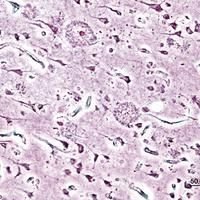

Image: Getty